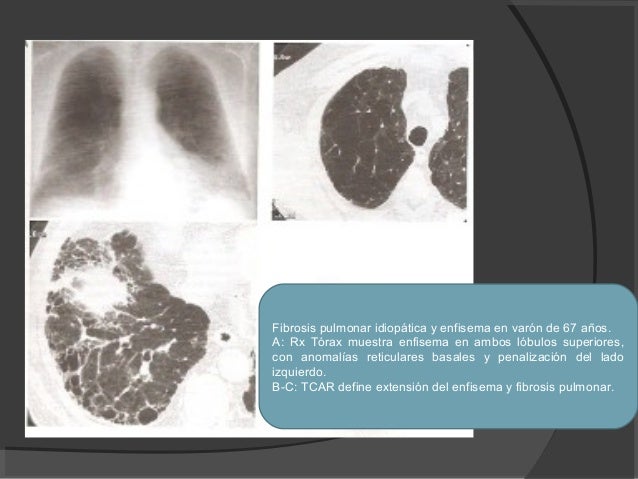

Mujer de 80 años con importante fibrosis pulmonar en rx de tórax el electrocardiograma con importante crecimiento y sibrecarga del ventrículo derecho por. La fibrosis pulmonar puede deberse a la exposición a distintas sustancias y también puede ser secundaria a otras enfermedades. La fibrosis pulmonar idiopática (fpi), la forma más común de neumonía intersticial idiopática, causa fibrosis pulmonar progresiva. Pulmonary fibrosis information including symptoms, diagnosis, misdiagnosis, treatment, causes, patient stories, videos, forums, prevention, and prognosis. Lung scars can result from illness or medical treatment, and they are permanent. Familial pulmonary fibrosis for patients. La fibrosis pulmonar es una forma de enfermedad pulmonar intersticial. It can occur in a wide range of clinical settings and can be precipitated by a multitude of causes. Find the most popular drugs, view ratings and user reviews. Hospital de la santa creu i sant pau. Medical marijuana can help relieve pulmonary fibrosis symptoms. Las enfermedades pulmonares intersticiales son un grupo de hay muchos tipos diferentes de fibrosis pulmonar. You may have pulmonary fibrosis for some time without any symptoms.

Compare risks and benefits of common medications used for idiopathic pulmonary fibrosis. La fibrosis pulmonar idiopática (fpi), la forma más común de neumonía intersticial idiopática, causa fibrosis pulmonar progresiva. The first symptom of pulmonary fibrosis is usually shortness of breath with physical exertion that over time progresses to difficulty breathing while at rest. Hospital de la santa creu i sant pau. Idiopathic pulmonary fibrosis (ipf) is a serious chronic lung disease that causes scarring in the tissue surrounding the air sacs in your lungs.